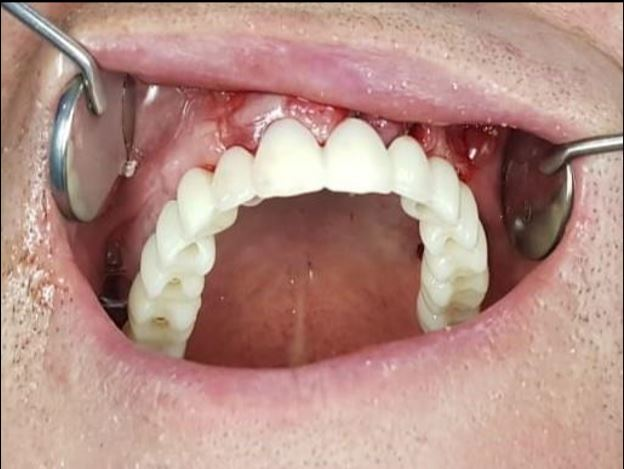

What is a healing cap on a dental implant?

A healing abutment, also known as a healing cap or gingival massage, can help promote soft tissue and hard tissue around the implant. The healing cap also protects the main part of the implant from plaque and debris accumulation. This may interest you : Dentist Plate. They are often mounted on top of the implant.